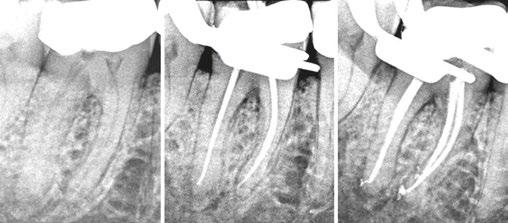

Figures 1A-1C: 1A. Preoperative X-ray. 1B. Immediate postoperative X-ray. 1C. Follow-up after 9 years and 10 months

Of the total, 29 had long-term radiographic follow-ups that ranged from a minimum of 6 months to a maximum of 25 years, with an average of 5 years, 4 months. Of the cases with radiographic follow-ups, 28 were considered successful and one failure (Table 2). Of the successful cases, 17 corresponded to treatments and 11 to retreatments (Figures 1A, 1B, 1C, and 2A, 2B, 2C). The tooth considered failed was a retreatment.

The radiographic appearances that generates the IRR are varied. The most common one observed in the present study was a circular shape with regular and symmetrical walls specially in single-rooted teeth (Figure 4A), although there were also some

Figures 2A-2C: 2A. Preoperative X-ray. 2B. Immediate postoperative X-ray. 2C. Follow-up after 18 years and 6 months

Figures 3A-3C: 3A. Preoperative X-ray. 3B. Immediate postoperative X-ray. 3C. Follow-up after 4 years